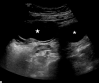

Case presentation: A 16-year-old female presented to the emergency department with acute onset of right lower quadrant abdominal pain for several hours. The patient was afebrile and physical examination was notable for isolated tenderness in the right lower quadrant. Ultrasound and computed tomography demonstrated an adnexal cystic structure. Pelvic magnetic resonance imaging was ordered to better characterize the pathology.